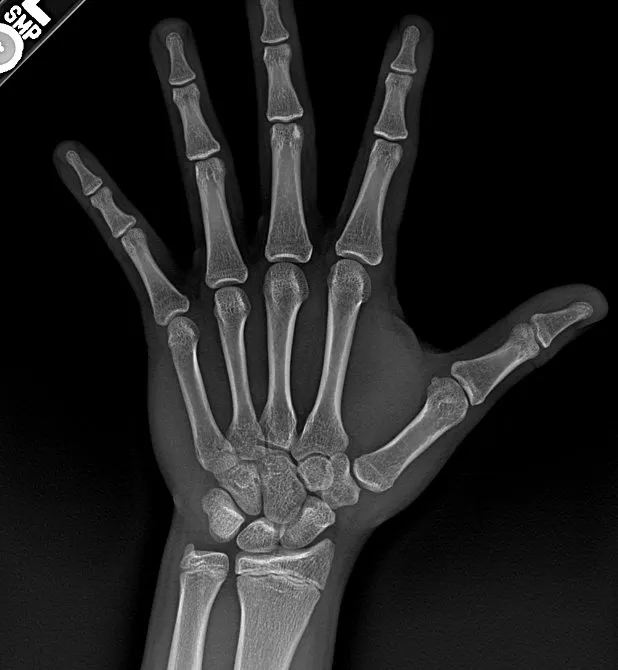

clearly fucking openView attachment 4942778

Is 5'10" feasible w/ roids? Frauding's zero at my current heightThere is a bit left

take 350mg testView attachment 4942778

what is infrigatiniba bit but your plates could be almost fully closed and infig would get you hella inches lol